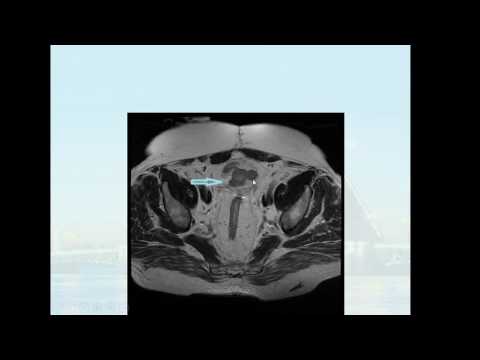

Доклад: «МР-диффузия в уточнённой диагностике рака мочевого пузыря».

Петров Иван Николаевич врач-рентгенолог рентгеновского отделения СПб ГБУЗ «Городская Мариинская больница», аспирант кафедры онкологии с курсом лучевой диагностики и терапии СПбГУ